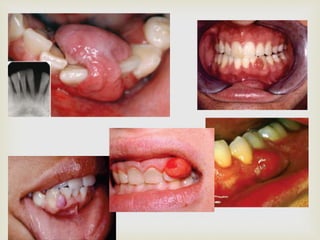

 Flat/ raised lesion of the mucosa

 Deep red/ bluish red in colour

 Readily compressible and fills slowly when released

 Common sites: lips, tongue, buccal mucosa and

palate

 Usually traumatised, undergoes ulceration and

secondary infection

 INTRAMUSCULAR AND CENTRAL

HEMANGIOMAS are also reported in the oral cavity

HEMANGIOMA

Oral manifestations…

 Central hemangioma:

 Occur in maxilla and mandible; 2/3rds in mandible

 First 2 decades of life

 bone destructive lesion: honey comb appearance in

radiograph

 Root resorption is seen in some cases; vitality is not

affected